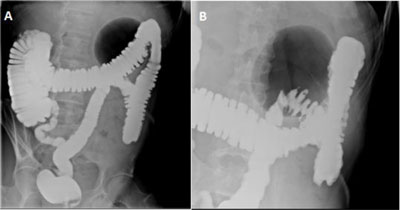

Figure 2

Gastrografin enema in standing position shows (A) a well-defined large gas-filled cavity of 9.7 cm in the left hypochondrium with neither air-fluid level nor extravasation of the contrast agent (balloon sign) and (B) focalized diverticular disease.